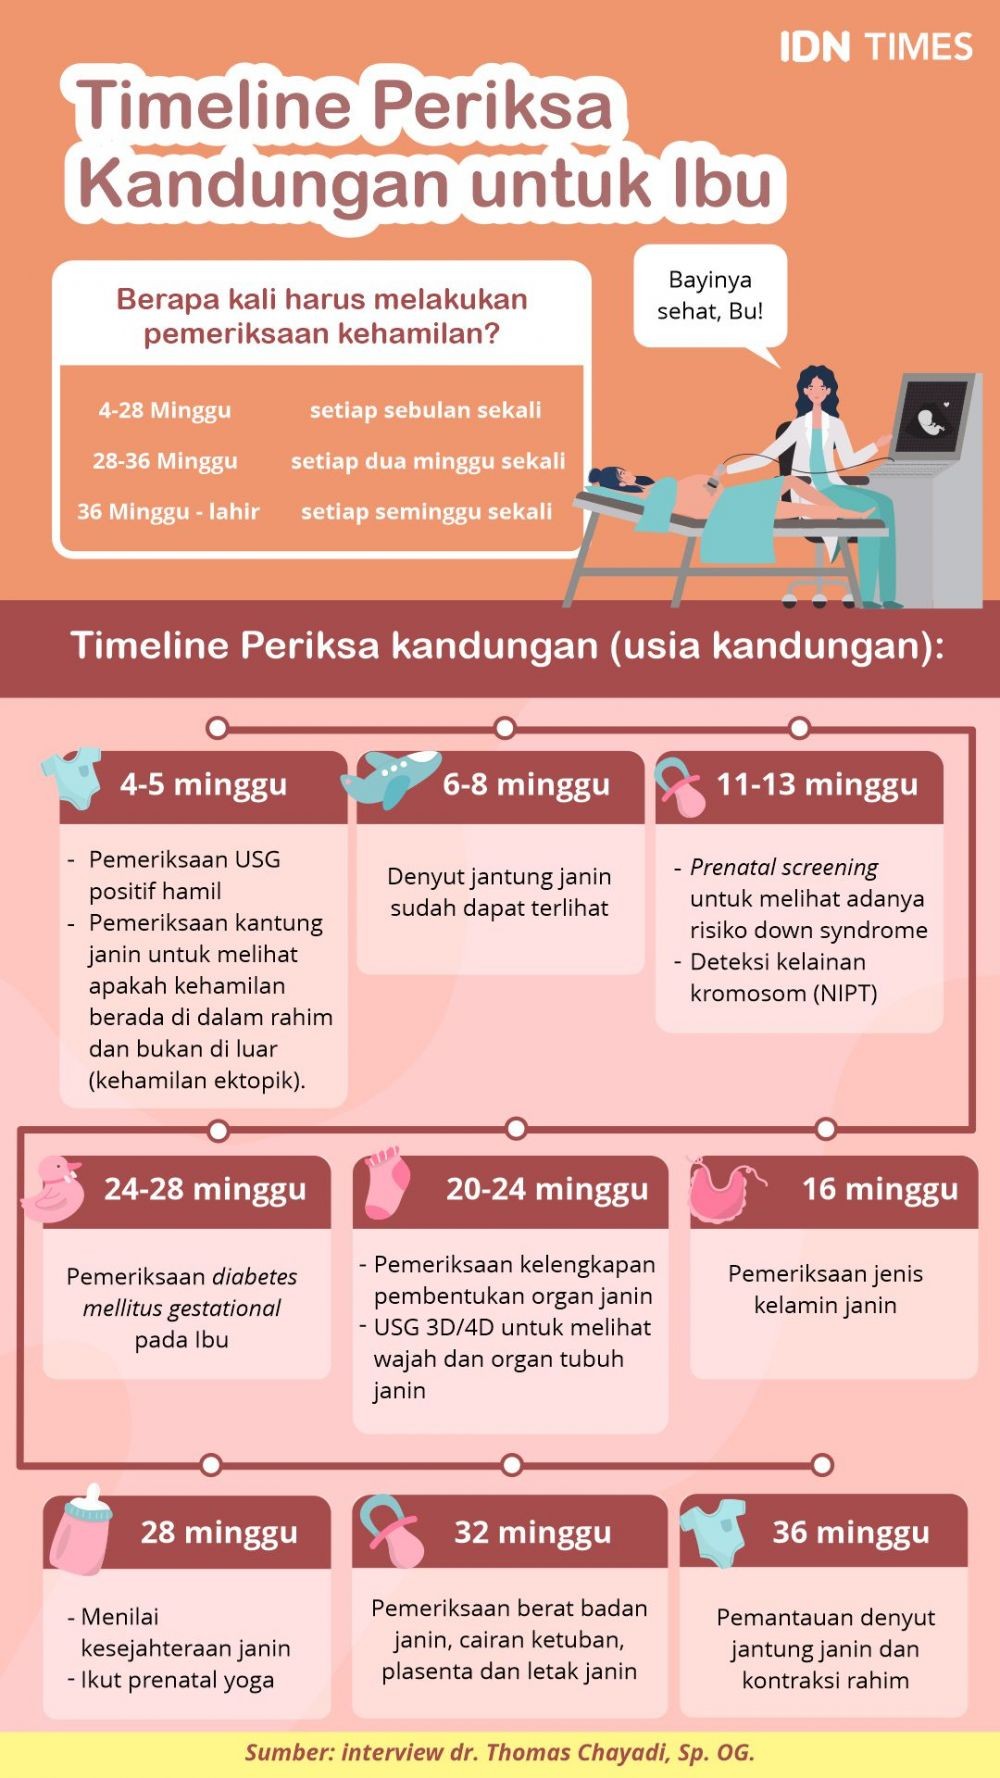

Infografis Timeline Periksa Kandungan Untuk Ibu Hamil

Infografis Timeline Periksa Kandungan Untuk Ibu Hamil